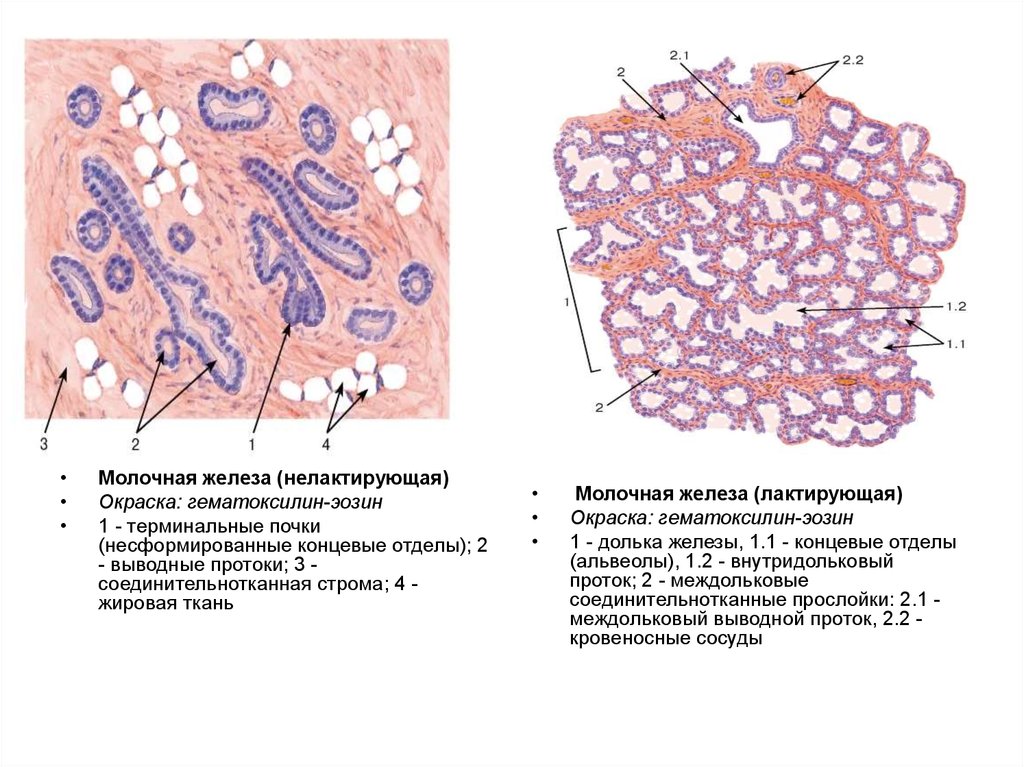

Исследование: микропрепарат молочной железы в медицине

Раздел: Снимки-откровения